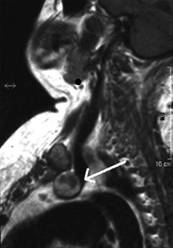

Femeie de 65 ani. De 10 ani prima interventie de

tiroidectomie totala pentru neoplazie papilara infiltranta in tesutul muscular,

cu metastaze linfonodale. Terapie cu Iodi 131 in primii 5 ani.

Voluminoasa tumefactie laterocervicala dreapta (16 cc ) si paratraheala stanga

(3 cc), pozitiva la citoaspiratie pentru recidiva de neoplazie papilara.

Aceeasi de

65 ani. Nu se evidentiaza vascularizatie intratumorale

Aceeasi pacienta. IRM evidentiaza o formatiune neevidentiata ecografic, metastatica histologic.